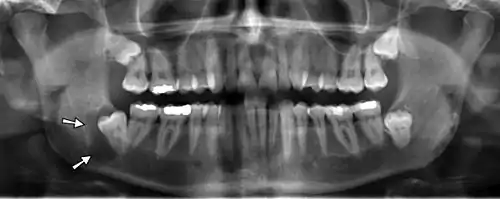

| Denigerous cyst of the right jaw around an impacted wisdom tooth | |